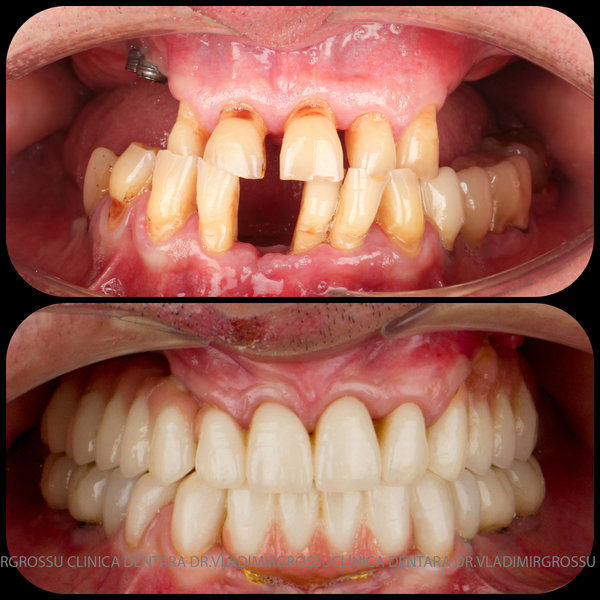

Cazuri clinice conceptul All-on-6